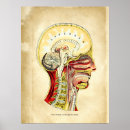

Vintage Illustration Human System Poster

PriceCA$52.05